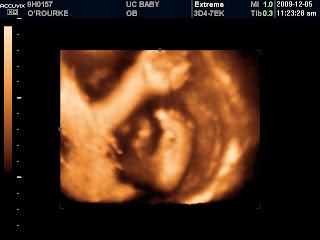

Even though Mommy and Daddy are photographers, this little one decided to be a little camera shy. Our baby decided that instead of posing for the camera, s/he was comfortable cuddling up to Mommy on its side and didn’t really want to wake up. We got some beautiful shots of our baby in profile: